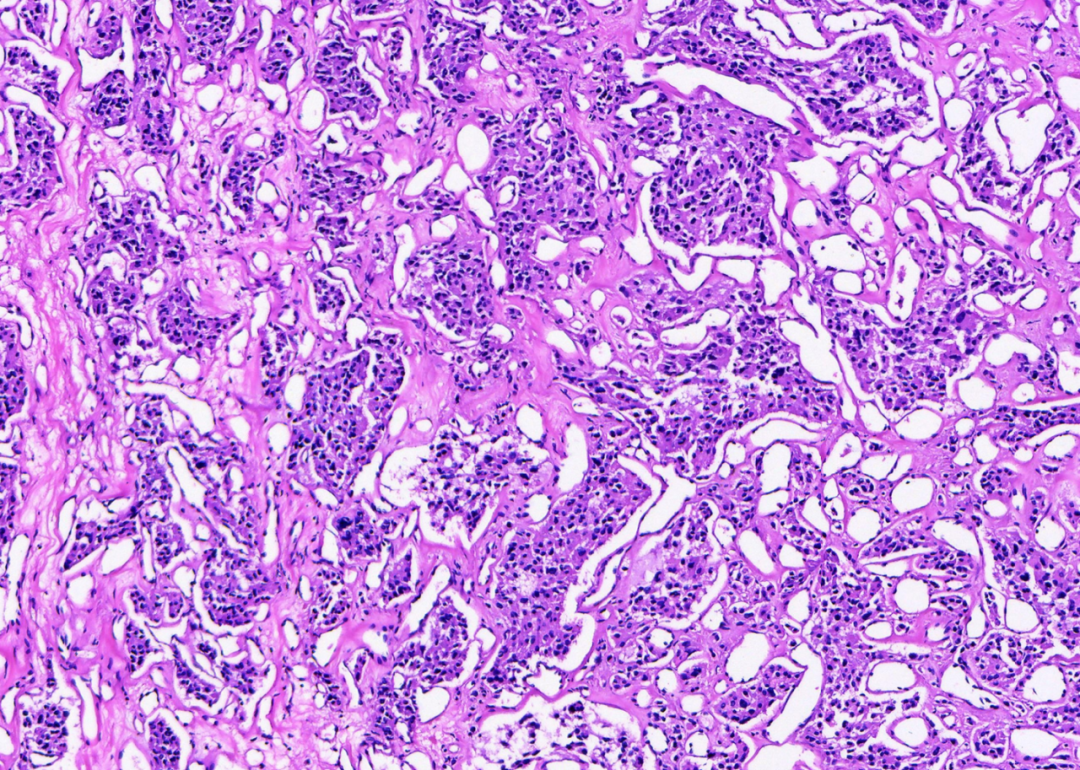

• 术中及术后镜下形态 (H&E):肿瘤细胞呈特征性的巢状(Zellballen)或腺泡状排列。细胞巢由两种成分构成:中央是胞浆丰富、嗜酸性颗粒状、核染色质呈“椒盐样”的多边形主细胞;周边则围绕着不明显的梭形支持细胞。细胞巢之间是极为丰富的血窦网络。第一印象:形态学高度指向副神经节瘤。

• 关键证据的捕获:这种经典的“Zellballen”结构,是病理医生脑海中诊断副神经节瘤的“警铃”。它与最初怀疑的生殖细胞肿瘤或其他腹膜后肿瘤(如平滑肌肉瘤、脂肪肉瘤)的形态截然不同。

• 诊断解读:诊断的核心,在于识别这种教科书般的组织学结构。它就像肿瘤的“指纹”,具有高度特异性。至此,病理形态学已经彻底扭转了临床的初步诊断方向,为这个“巨物”验明了正身。

图1. H&E染色清晰显示副神经节瘤经典的“细胞巢”(Zellballen)结构